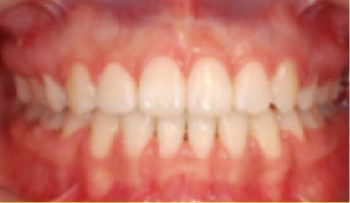

교정치료 Before&After

After